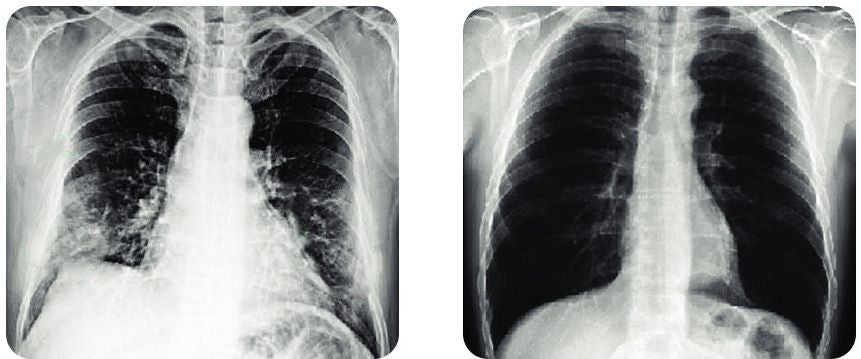

Emma Emerson

I've been using this spray for about 5 weeks and I'm just thrilled with the result, the picture below is the best proof of the change.

Emma Emerson

I've been using this serum for about 5 weeks and I'm just thrilled with the result, the picture below is the best proof of the change.

Emma Emerson

I've been using this serum for about 5 weeks and I'm just thrilled with the result, the picture below is the best proof of the change.